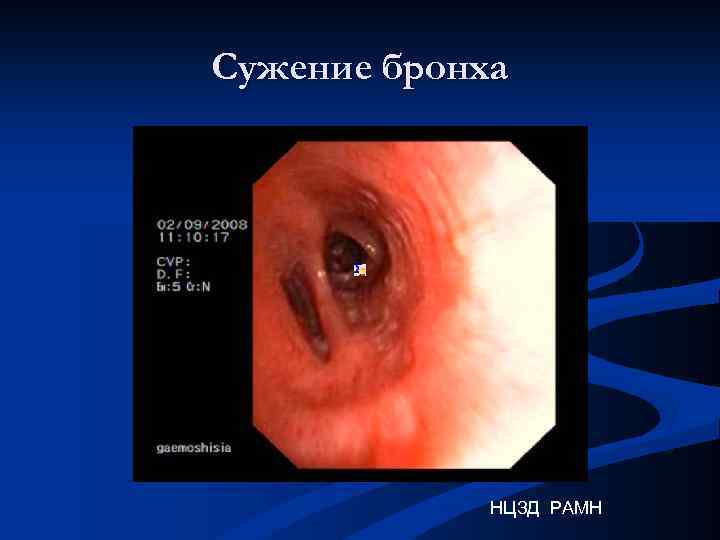

Сужение бронха НЦЗД РАМН